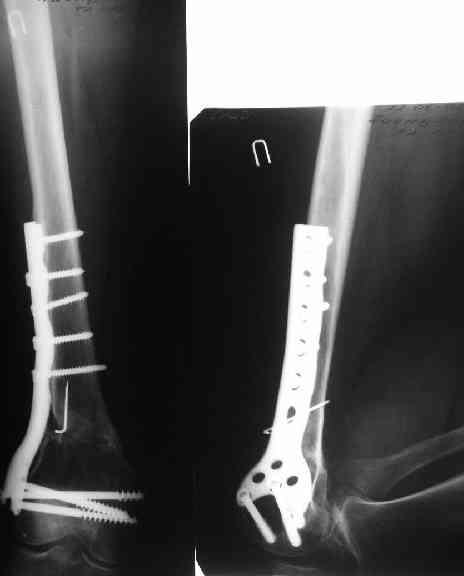

В приложении пример, как их использовали после остеотомии бедра по поводу сросшегося с вальгусом перелома, чтобы не дать гвоздю уйти во внутренний мыщелок.